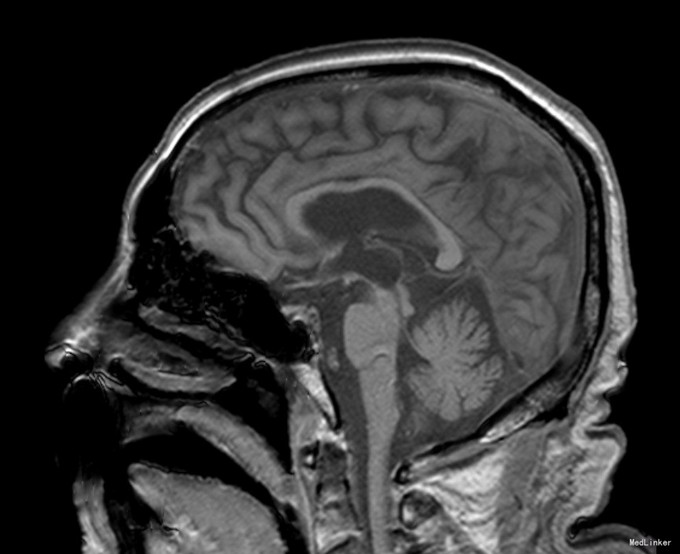

临床表现:(1)核上性眼肌麻痹:是PSP最具诊断价值的临床表现,出现早晚差异很大,一般在出现核上性眼肌麻痹时才得以诊断。早期表现为两眼追随性下视麻痹、上视受限,逐渐发展成完全性垂直凝视麻痹,晚期侧视运动亦受累。自发性凝视较追踪性凝视更易受累,但核上性眼肌麻痹常在发病多年后才出现,给早期诊断造成困难。(2)帕金森综合征症状:常对称起病,步态不稳是最常见的首发症状,尤易向后跌倒,系眼-前庭功能障碍、躯干强直、少动所致。轴性肌强直是本病的另一特征,即颈肌及上部躯干肌强直比四肢强直明显,表现为身体笔直伴颈后仰的特殊体姿。(3)假性延髓性麻痹。(4)认知功能障碍与行为异常:认知功能障碍以皮质下痴呆为特征,表现为思维缓慢、健忘伴淡漠、抑郁及执行功能减退。晚期可出现睁闭眼失用症。 MRI特征:脑MR平扫可见第三脑室和脚间池变宽、中脑和四叠体萎缩、导水管周围FLAIR像高信号等改变,还可出现不同程度大脑皮质萎缩,以额叶明显。在MR正中矢状面T1加权像平扫,PSP以中脑顶盖萎缩为主,中脑嘴明显变尖,使中脑、脑桥和小脑整体上形似蜂鸟,称为“蜂鸟征”(humming bird sign)。PSP患者MR轴位可见中脑前后径明显缩短,谓之“鼠耳征”(mouse ears sign);同时,由于中脑被盖部外侧缘凹陷,也可表现为“牵牛花征”。